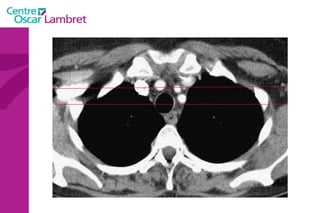

Les Troncs Supra Aortiques s’organisent autour de la trachée à leur origine. L’appareil circulatoire

Les Troncs SupraAortiques s’organisent autour de la trachée à leur origine. L’appareil circulatoire